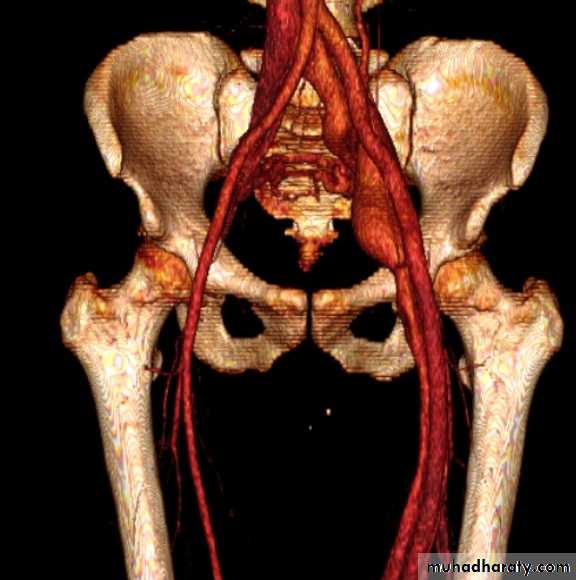

CT angio